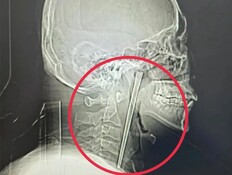

מחריד: רב עם אשתו על הגשר, והכל הסתבך בשנייה

הילדים נותרו עם טראומה לכל החיים